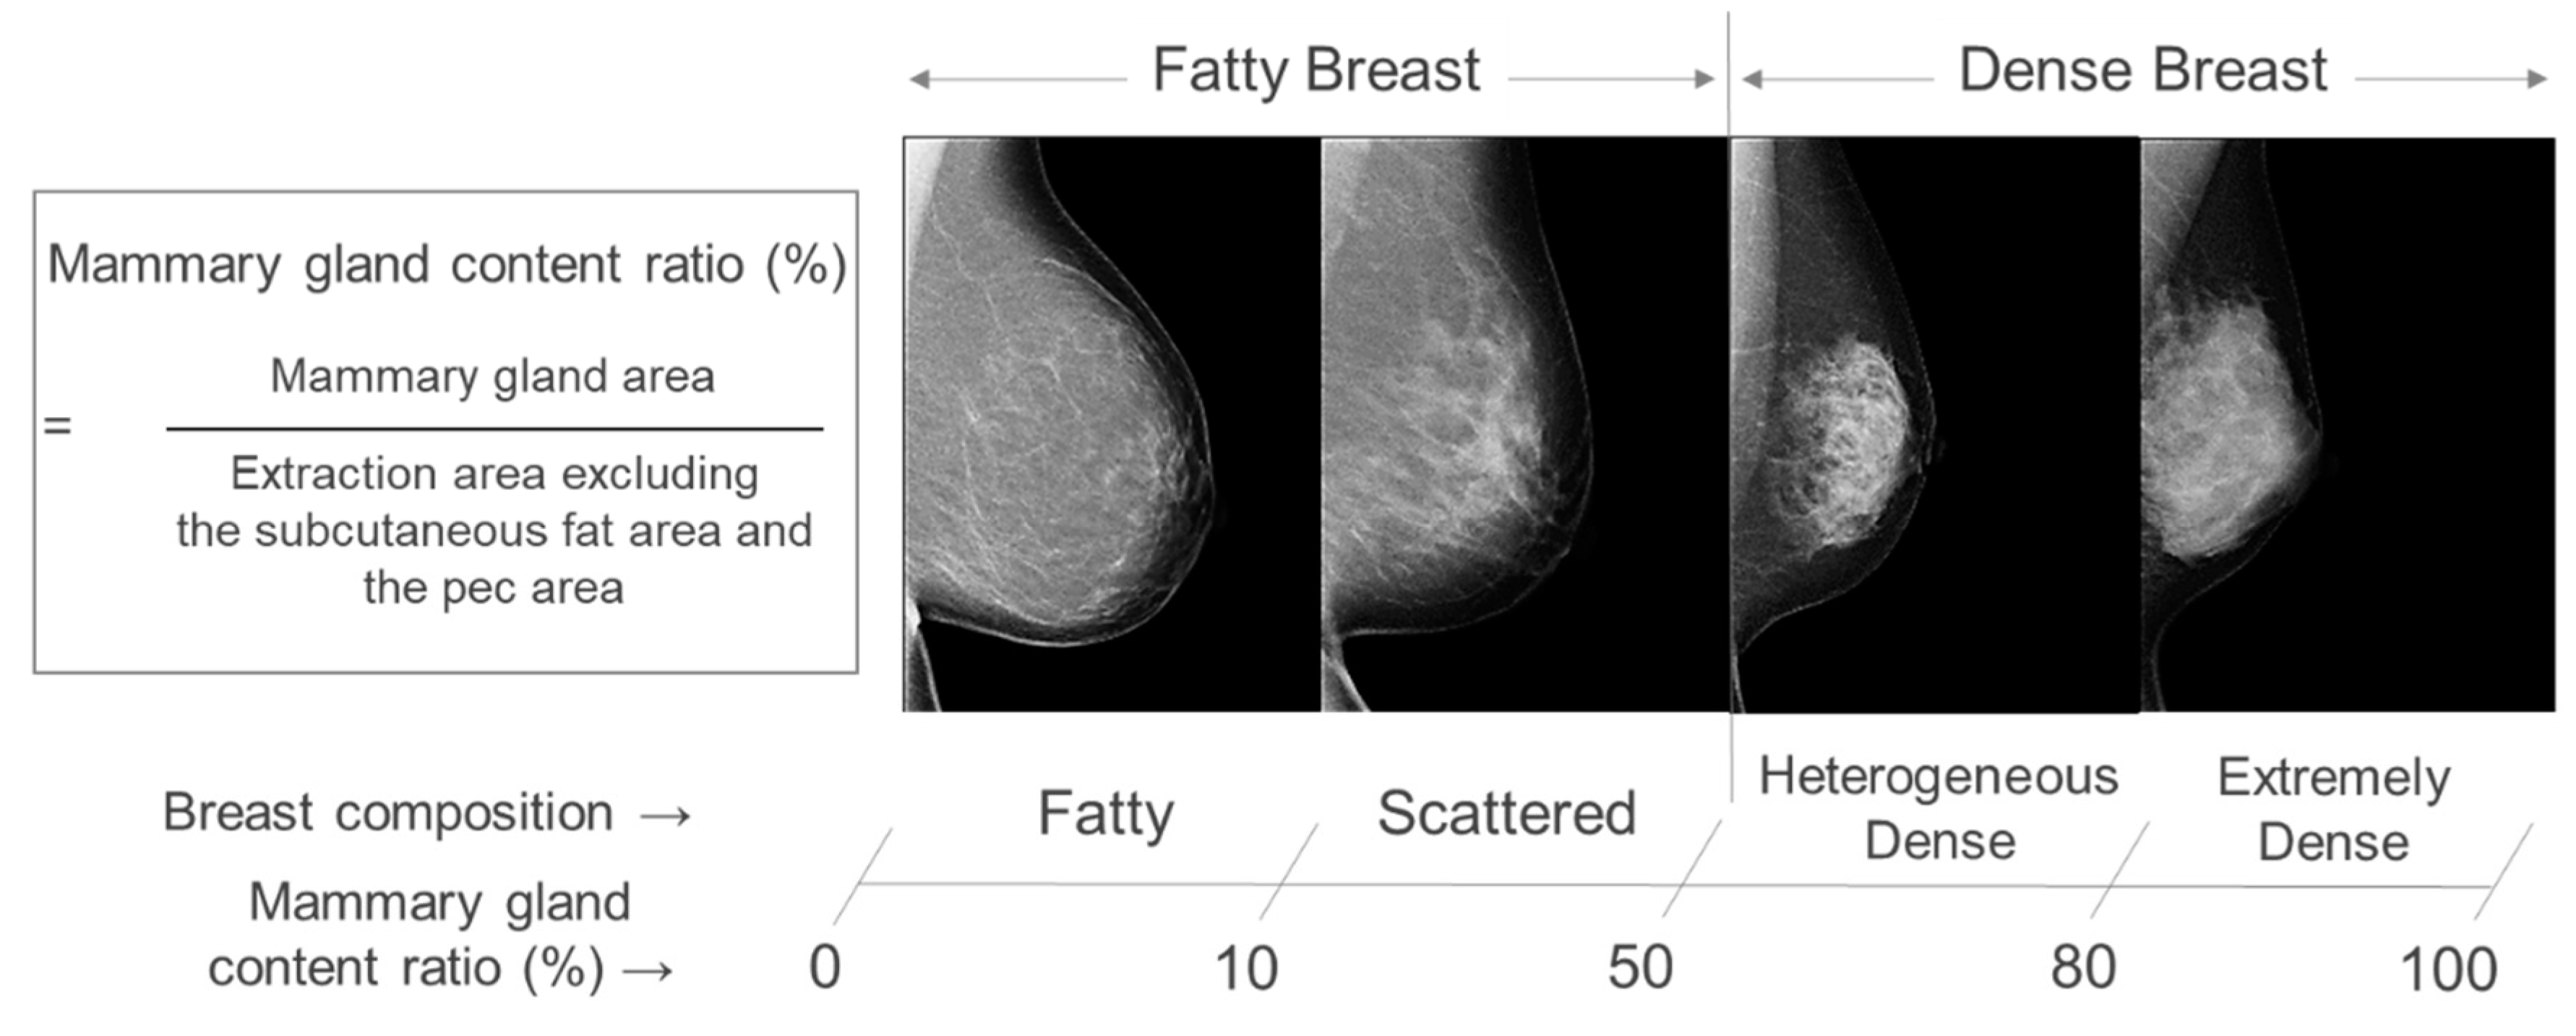

1. Introduction

2. Materials and Methods